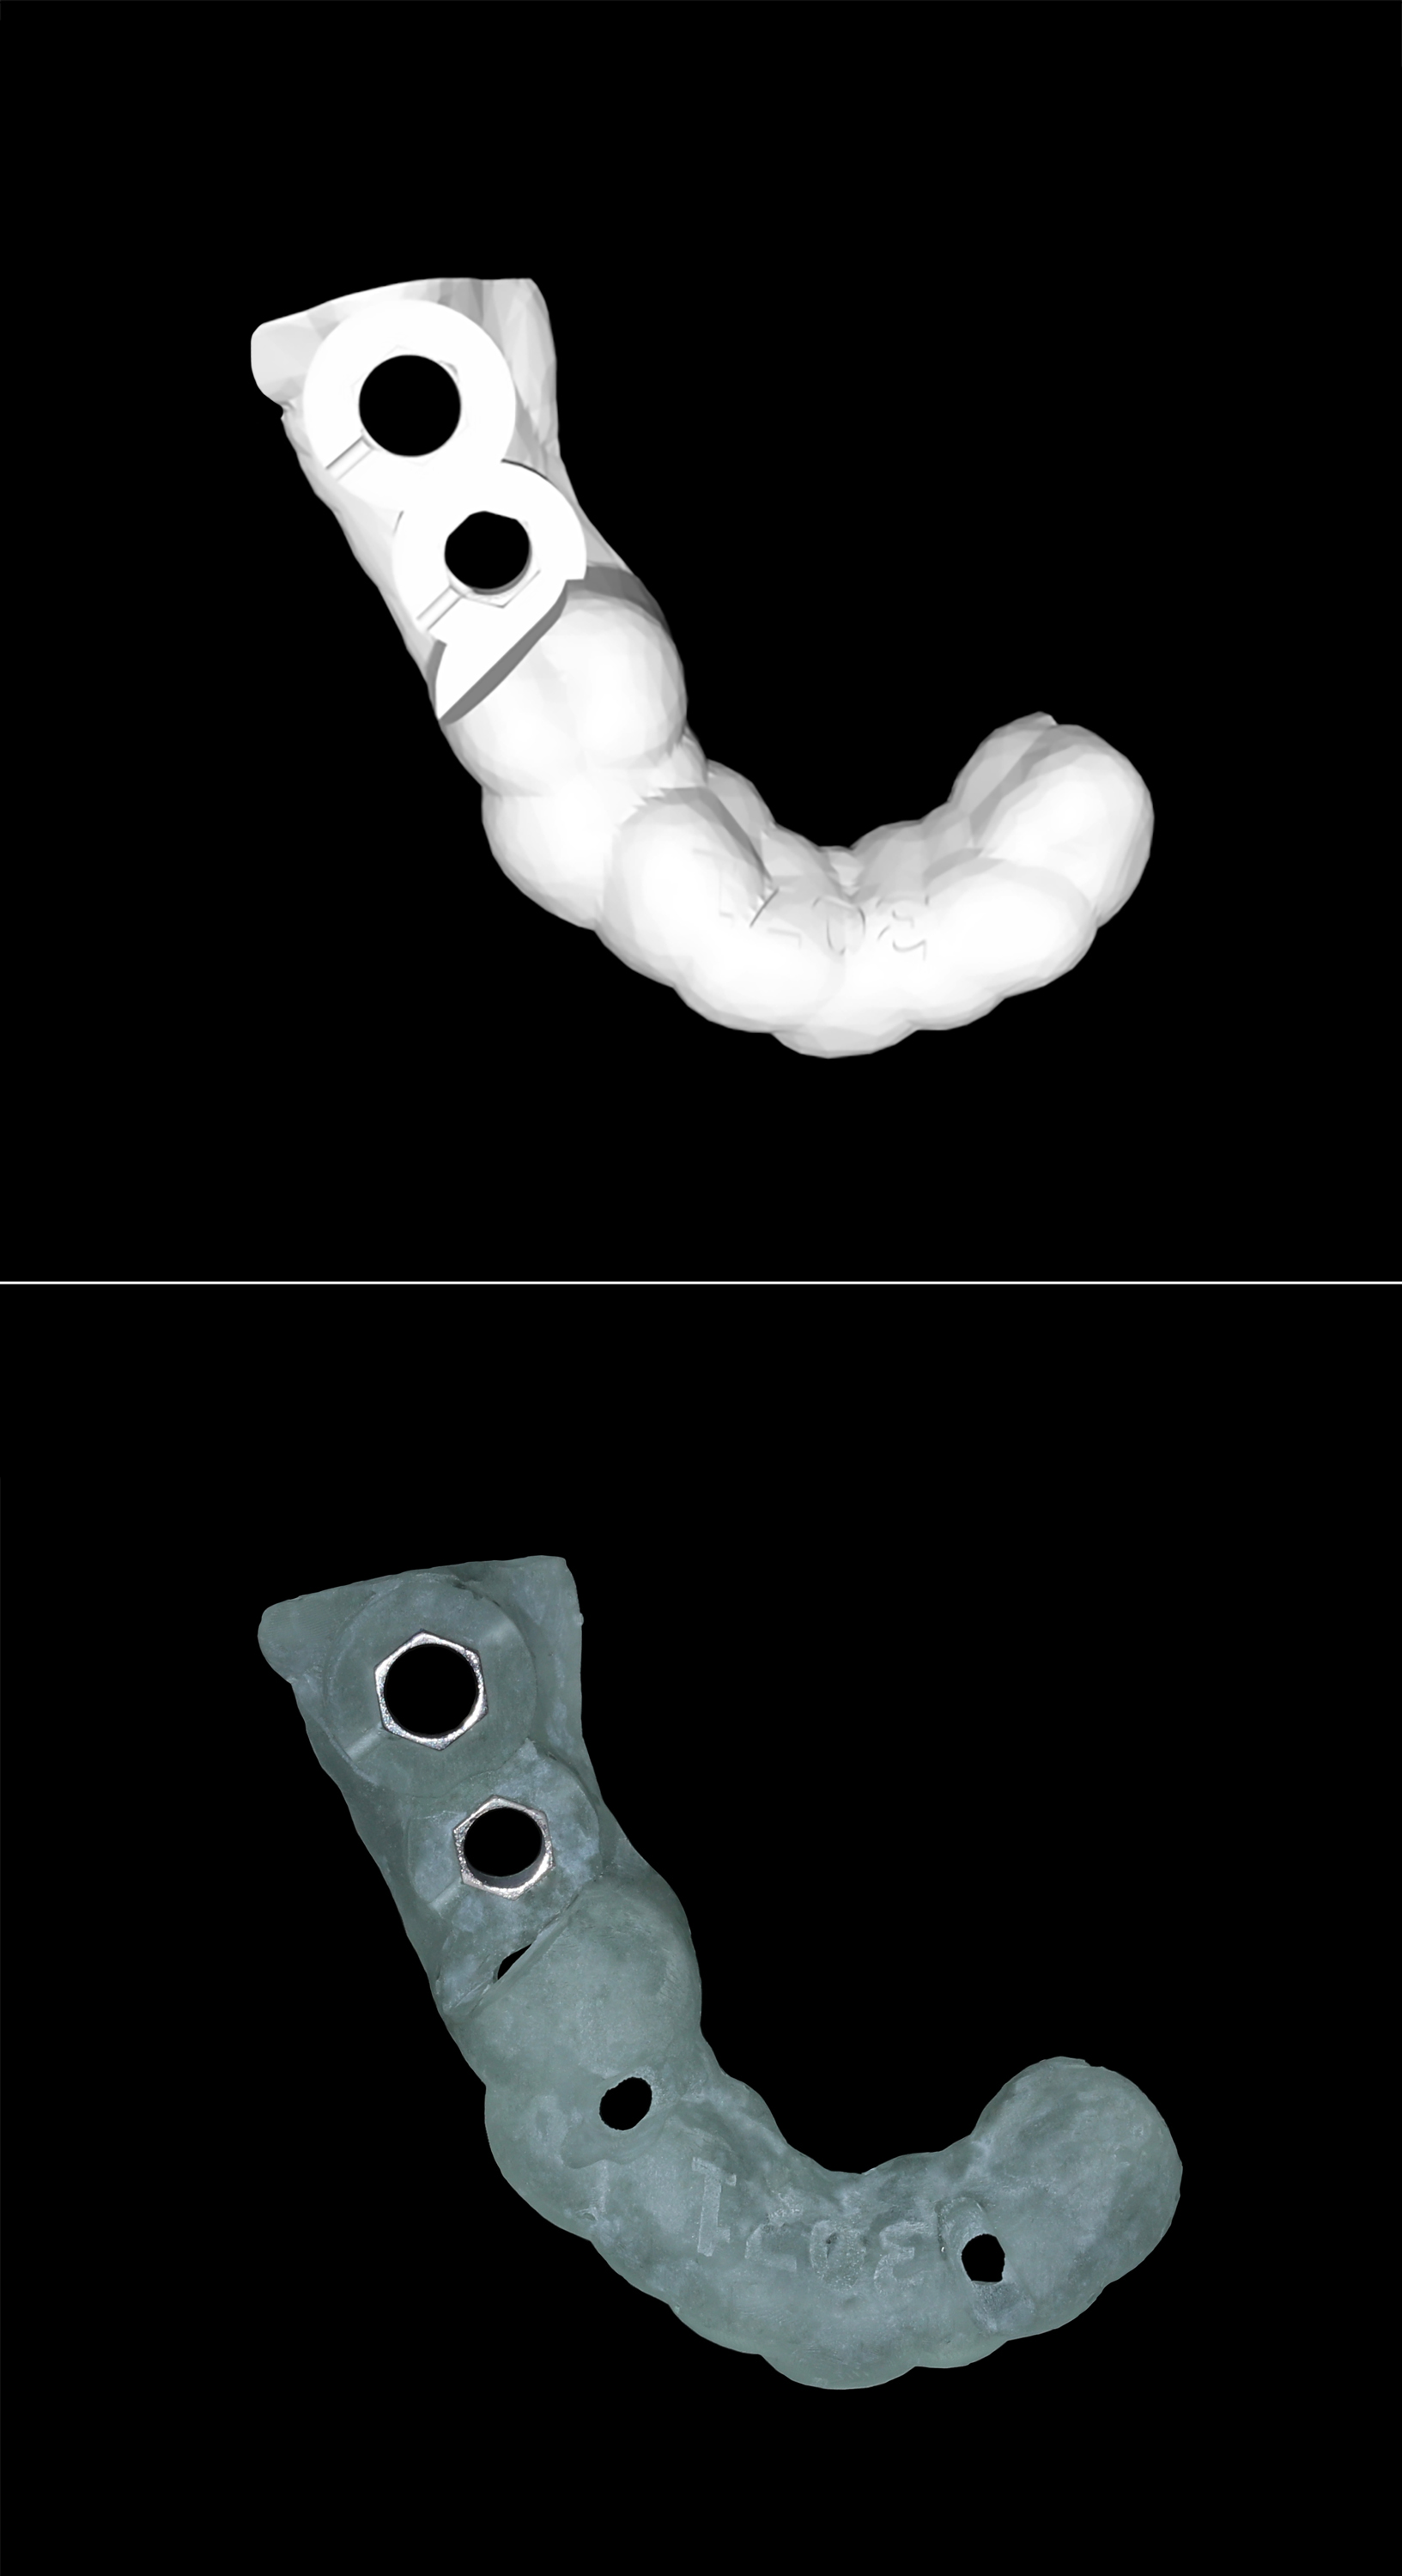

Πάνω: Το ψηφιακό αρχείο του χειρουργικού νάρθηκα - Κάτω: Ο χειρουργικός νάρθηκας εκτυπωμένος από 3D εκτυπωτή

Ο τελικός σχεδιασμός στάλθηκε σε εξειδικευμένο εμφυτευματολογικό κέντρο στη Γερμανία, όπου κατασκευάστηκε εξατομικευμένος χειρουργικός νάρθηκας, βασισμένος στην ανατομία της ασθενούς και τον ψηφιακό σχεδιασμό.

Η τοποθέτηση των δύο εμφυτευμάτων πραγματοποιήθηκε με απόλυτη ακρίβεια, χρησιμοποιώντας τον τρισδιάστατα εκτυπωμένο χειρουργικό οδηγό. Η χρήση ψηφιακής τεχνολογίας εξασφάλισε ταχύτητα, χειρουργική ακρίβεια χιλιοστού, μηδαμινό τραύμα, και ελαχιστοποίηση των χειρουργικών επιπλοκών.